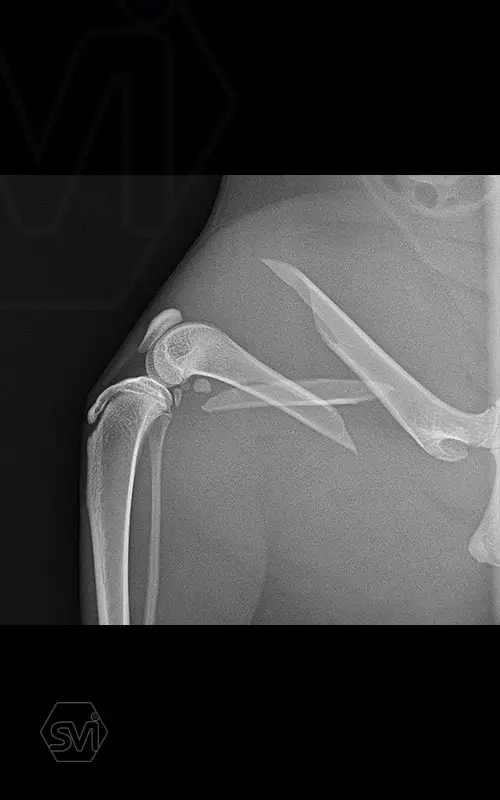

In our case, a middle third fragment fracture of a 10-month-old kitten was treated with a 2.0 polyaxial plate and a combination of 2.0 and 2.4 screws.

Esetünkben egy 10 hónapos cica középső harmadiszilánkos törését kezeltük 2,0 poliaxiális lemezzel és 2,0 és 2,4 csavarok kombinációjával.